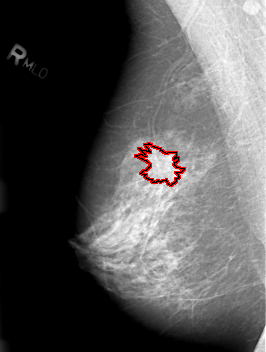

B_3012_1.RIGHT_MLO

RIGHT_MLO LINES 4216 PIXELS_PER_LINE 3192 BITS_PER_PIXEL 12 RESOLUTION 50 OVERLAY

FILE: B_3012_1.RIGHT_MLO.OVERLAY

TOTAL_ABNORMALITIES 1

ABNORMALITY 1

LESION_TYPE MASS SHAPE IRREGULAR MARGINS SPICULATED

ASSESSMENT 4

SUBTLETY 3

PATHOLOGY MALIGNANT

TOTAL_OUTLINES 1

BOUNDARY